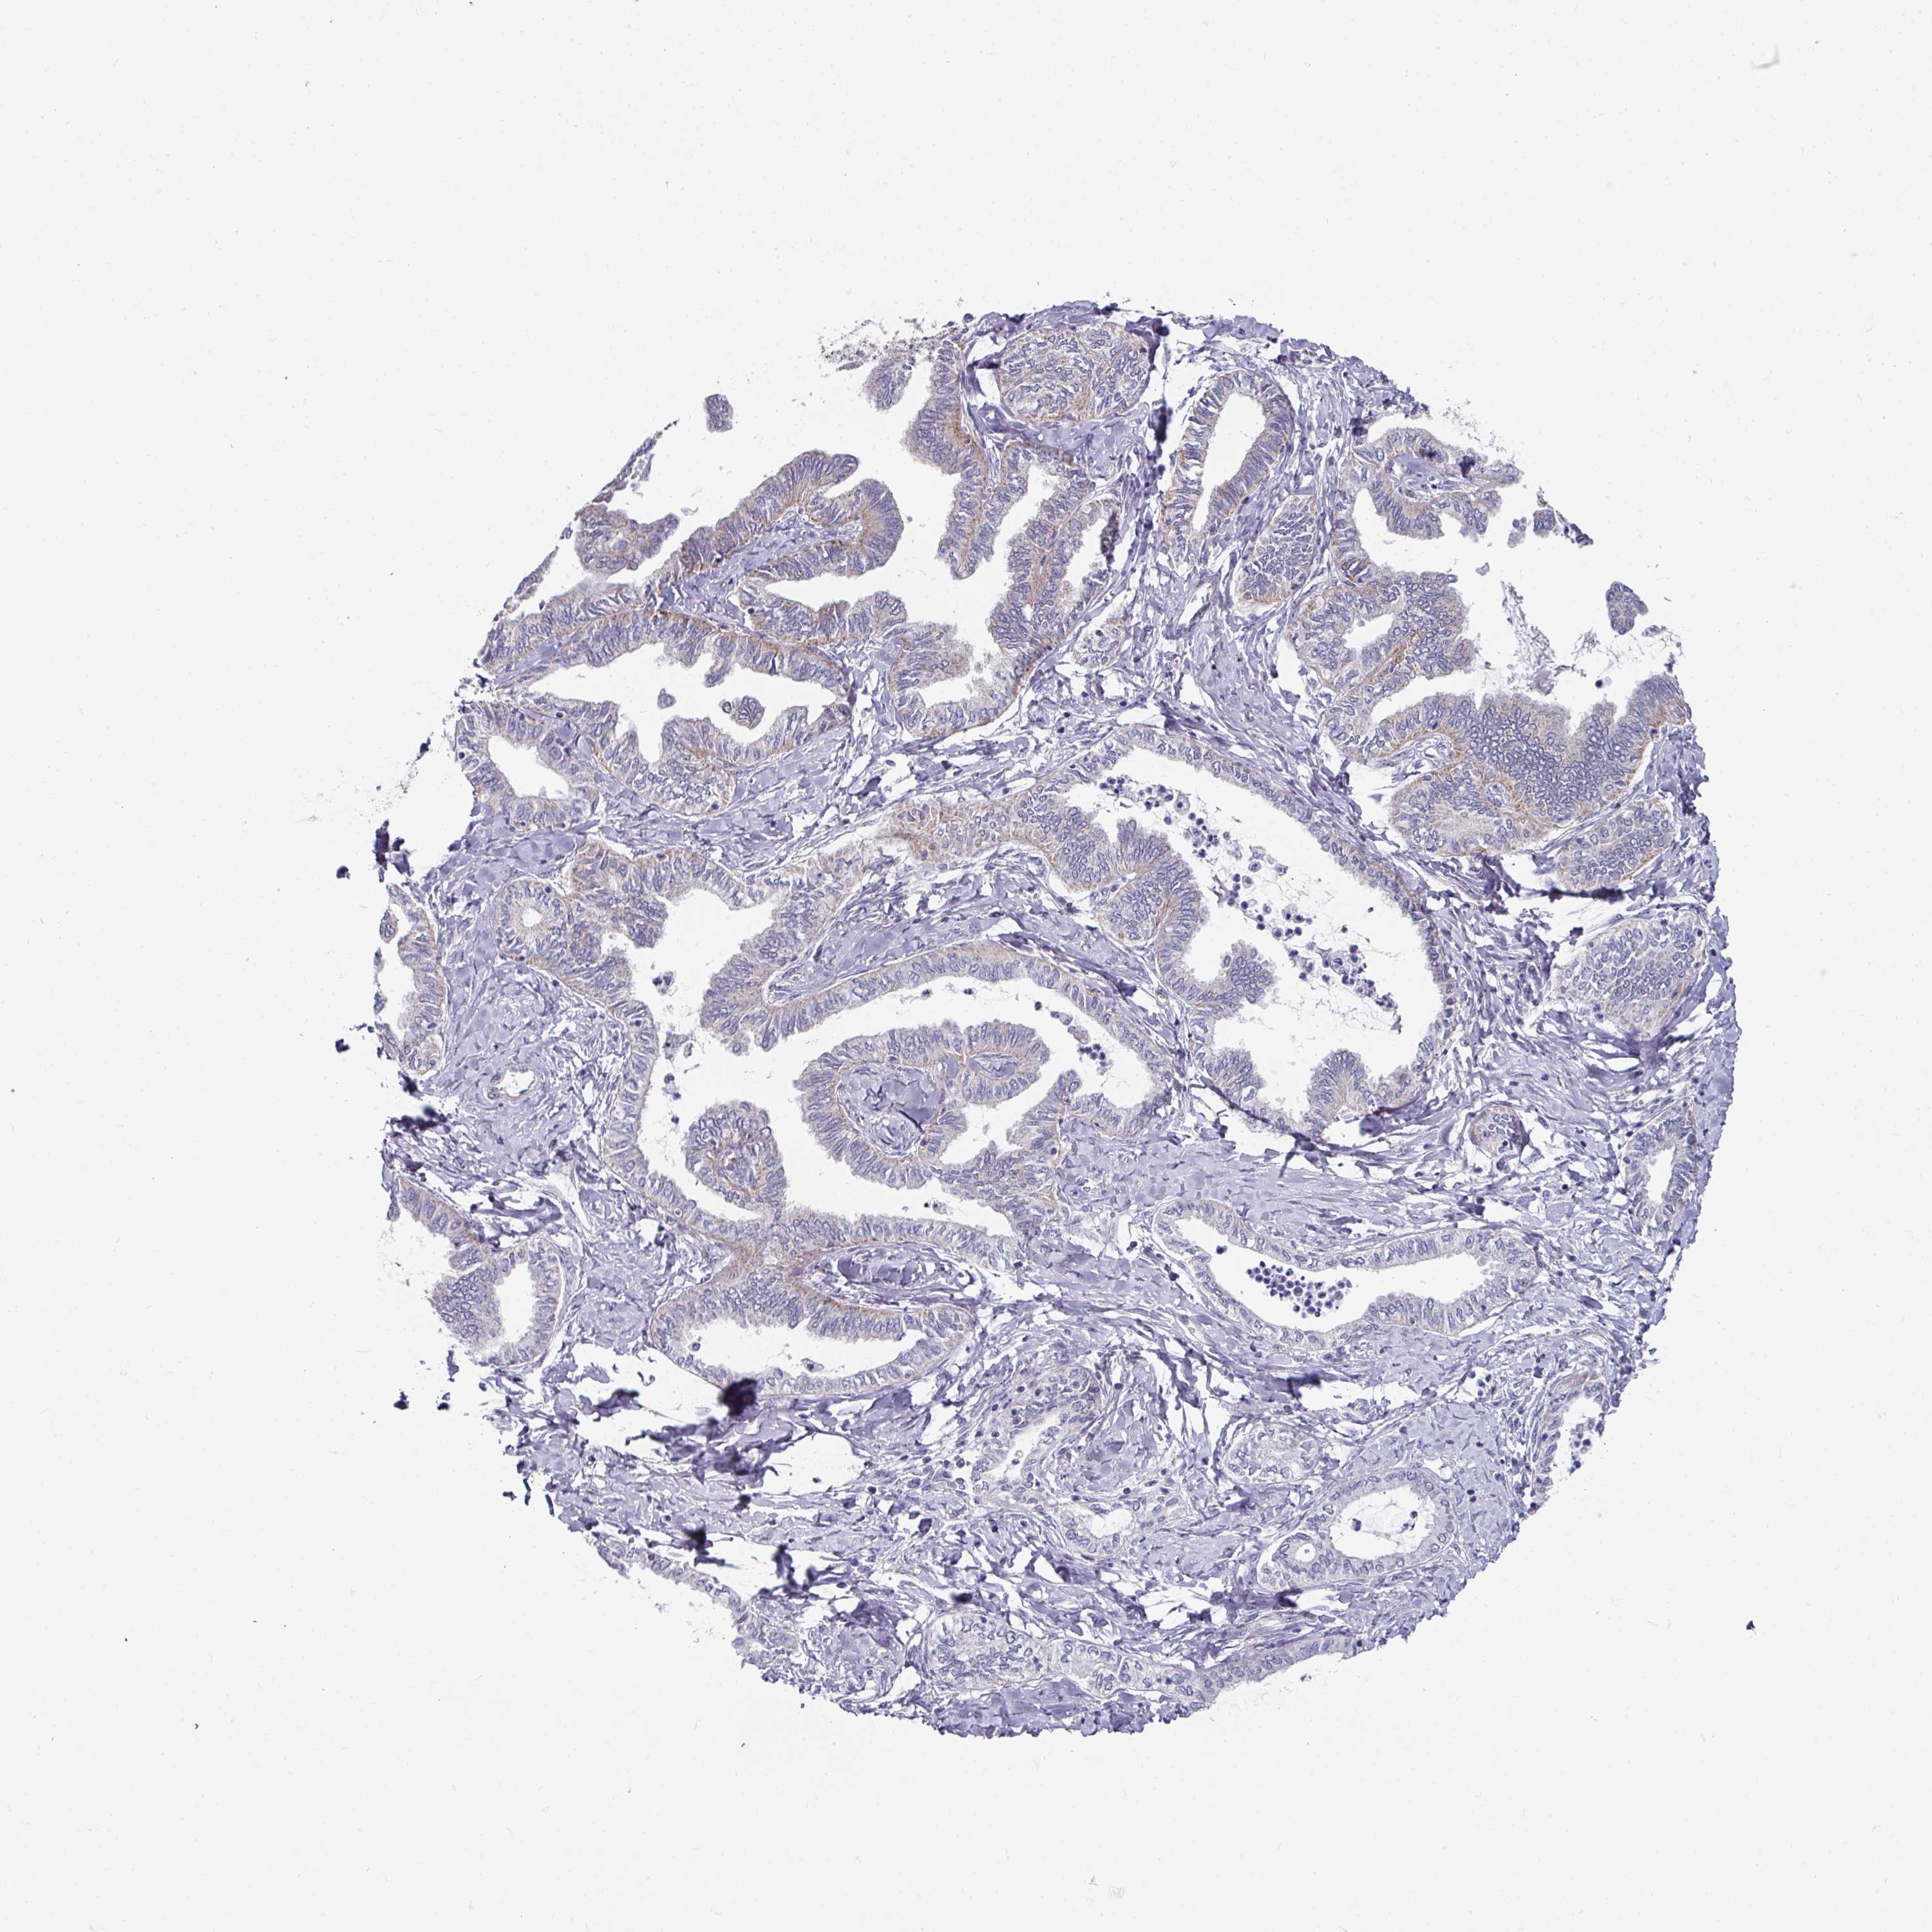

OVARIAN CANCER - Protein expressioni

A mouse-over function shows sample information and annotation data. Click on an image to view it in a full screen mode. Samples can be filtered based on level of antibody staining by selecting one or several of the following categories: high, medium, low and not detected. The assay and annotation is described here.

Note that samples used for immunohistochemistry by the Human Protein Atlas do not correspond to samples in the TCGA dataset.

Antibody stainingi

Antibody staining in the annotated cell types in the current human tissue is reported as not detected, low, medium, or high, based on conventional immunohistochemistry profiling in selected tissues. This score is based on the combination of the staining intensity and fraction of stained cells.

Each image is clickable and will lead to virtual microscopy that enables deeper exploration of all samples and also displays staining intensity scores, fraction scores and subcellular localization as well as patient and tissue information for each sample.

Antibody HPA048677

Antibody HPA056480

Antibody CAB011574

Cystadenocarcinoma, serous, NOS

Cystadenocarcinoma, mucinous, NOS

Adenocarcinoma, NOS

Carcinoma, endometroid

Carcinoma, NOS